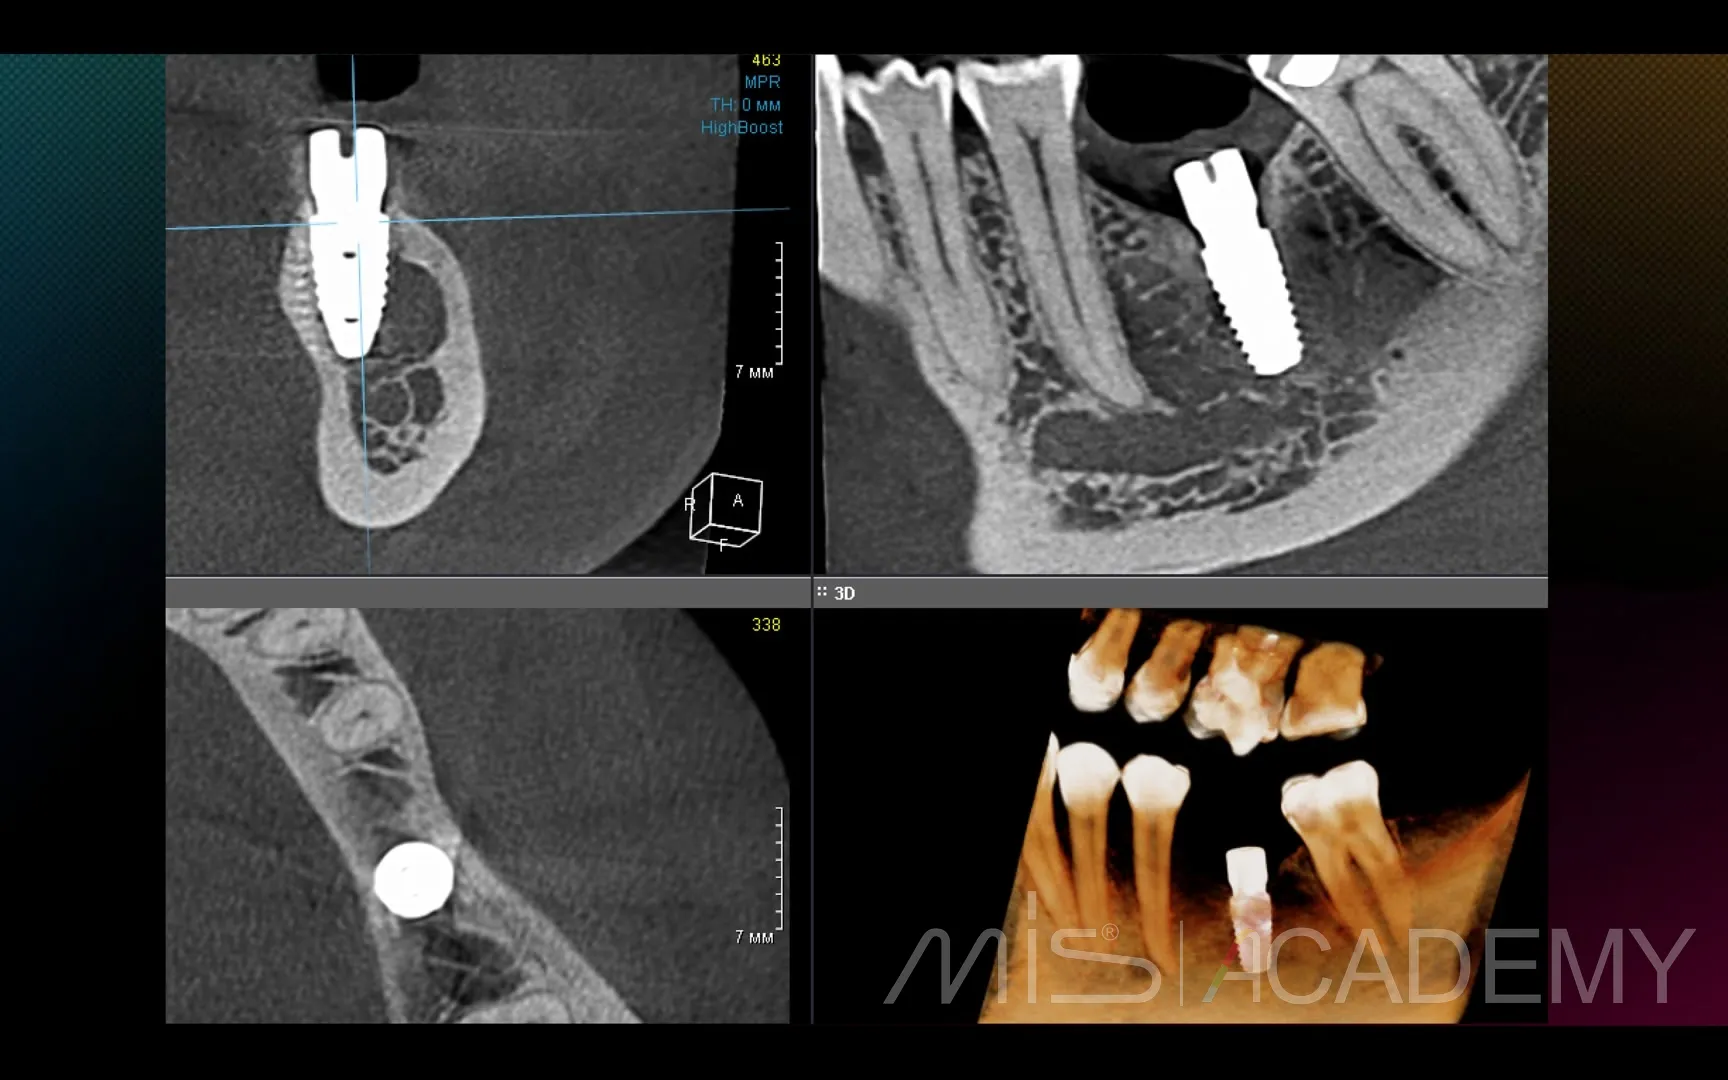

Промежуточный результат клинического кейса одномоментного закрытия рецессий и установки имплантата MIS C1 с CONNECT абатментом.